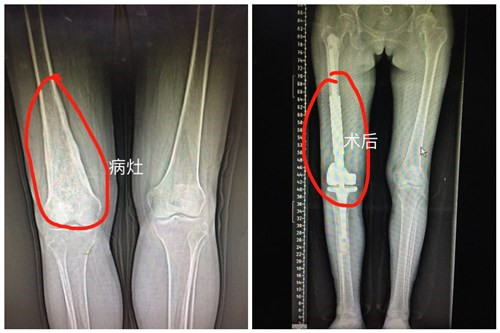

近日,临床医学院/附属医院骨科成功为一“股骨远端恶性肿瘤”患者行右股骨远端软骨肉瘤病灶切除+假体置换术,该手术为九江市首例。目前患者已康复出院。

患者杜女士,53岁,右膝关节反复疼痛一年多。辗转多家医院求医,均建议患者行截肢手术,不甘心的杜女士及家属慕名来临床医学院/附属医院骨科就诊。骨三科朱述浪主任带领的刘剑军等医师团队详细了解患者病情之后,立即召开病情讨论会,病理结果显示该患者所患为“软骨肉瘤”。为避免给患者带来身体及心理上的双重痛苦,改善其心理感受及提高生活质量,朱主任团队决定最大限度保留患者的肢体功能,并为患者制定了精准的手术方案及个性化的人工膝关节肿瘤假体。手术过程顺利,手术时长不到2小时,术中出血仅150ml,术后患者膝关节功能恢复良好,很快能下地活动。出院前患者握着医护人员的手说:“来附属医院求医是最正确的选择,不仅减轻我的病痛,同时让我感觉到你们的耐心、责任心,你们亲切的语言,微笑的脸庞,让病房充满了阳光,充满温馨。你们是最好的医护团队。”

据朱主任介绍,现代医学已迈入精准医疗时代,在骨肿瘤的精准治疗方面包括如何合理选择靶向药物和制定个体化治疗方案,骨肿瘤手术的个体化治疗是精准医疗不可或缺的一部分。骨三科在骨肿瘤个体化治疗的指导原则下,已初步对膝关节周围肿瘤患者根据个体定制人工膝关节假体置换手术,让饱受骨肿瘤困扰的患者免受截肢之苦。在骨肿瘤病方面,临床医学院/附属医院骨三科已紧跟现代医学发展的潮流,朝着未来的发展方向而不断革新技术,造福九江人民!